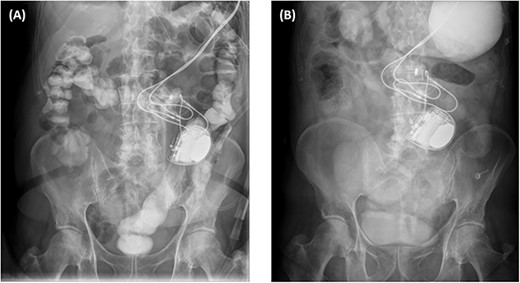

The abdominal computed tomography (CT) studies on all three recent admissions were consistent with SBO. The transition point was consistently seen in the right iliac fossa; with small bowel loops distended proximally with air-fluid levels and faecalised contents; and small bowel loops collapsed distally to the ileocaecal valve (Fig. 1A). There were no signs of bowel ischaemia or perforation. However, the preperitoneal ICD appeared to have migrated into the peritoneal cavity (Fig. 1B). On review of the serial abdominal CT studies over the past two years, the ICD was in a different intraperitoneal location each time (Fig. 2). The recurrent episodes of SBOs were thus believed to be related to the ICD, due to either intraperitoneal migration of the device or formation of adhesions from its placement, given the coinciding timeline.

Serial computed tomography studies from the six episodes of SBOs showing the abdominal ICD device (star) in a different intraperitoneal location each time — in March (A), April (B), and November (C) of 2019; November (D) and December (E) of 2020; and January (F) of 2021.